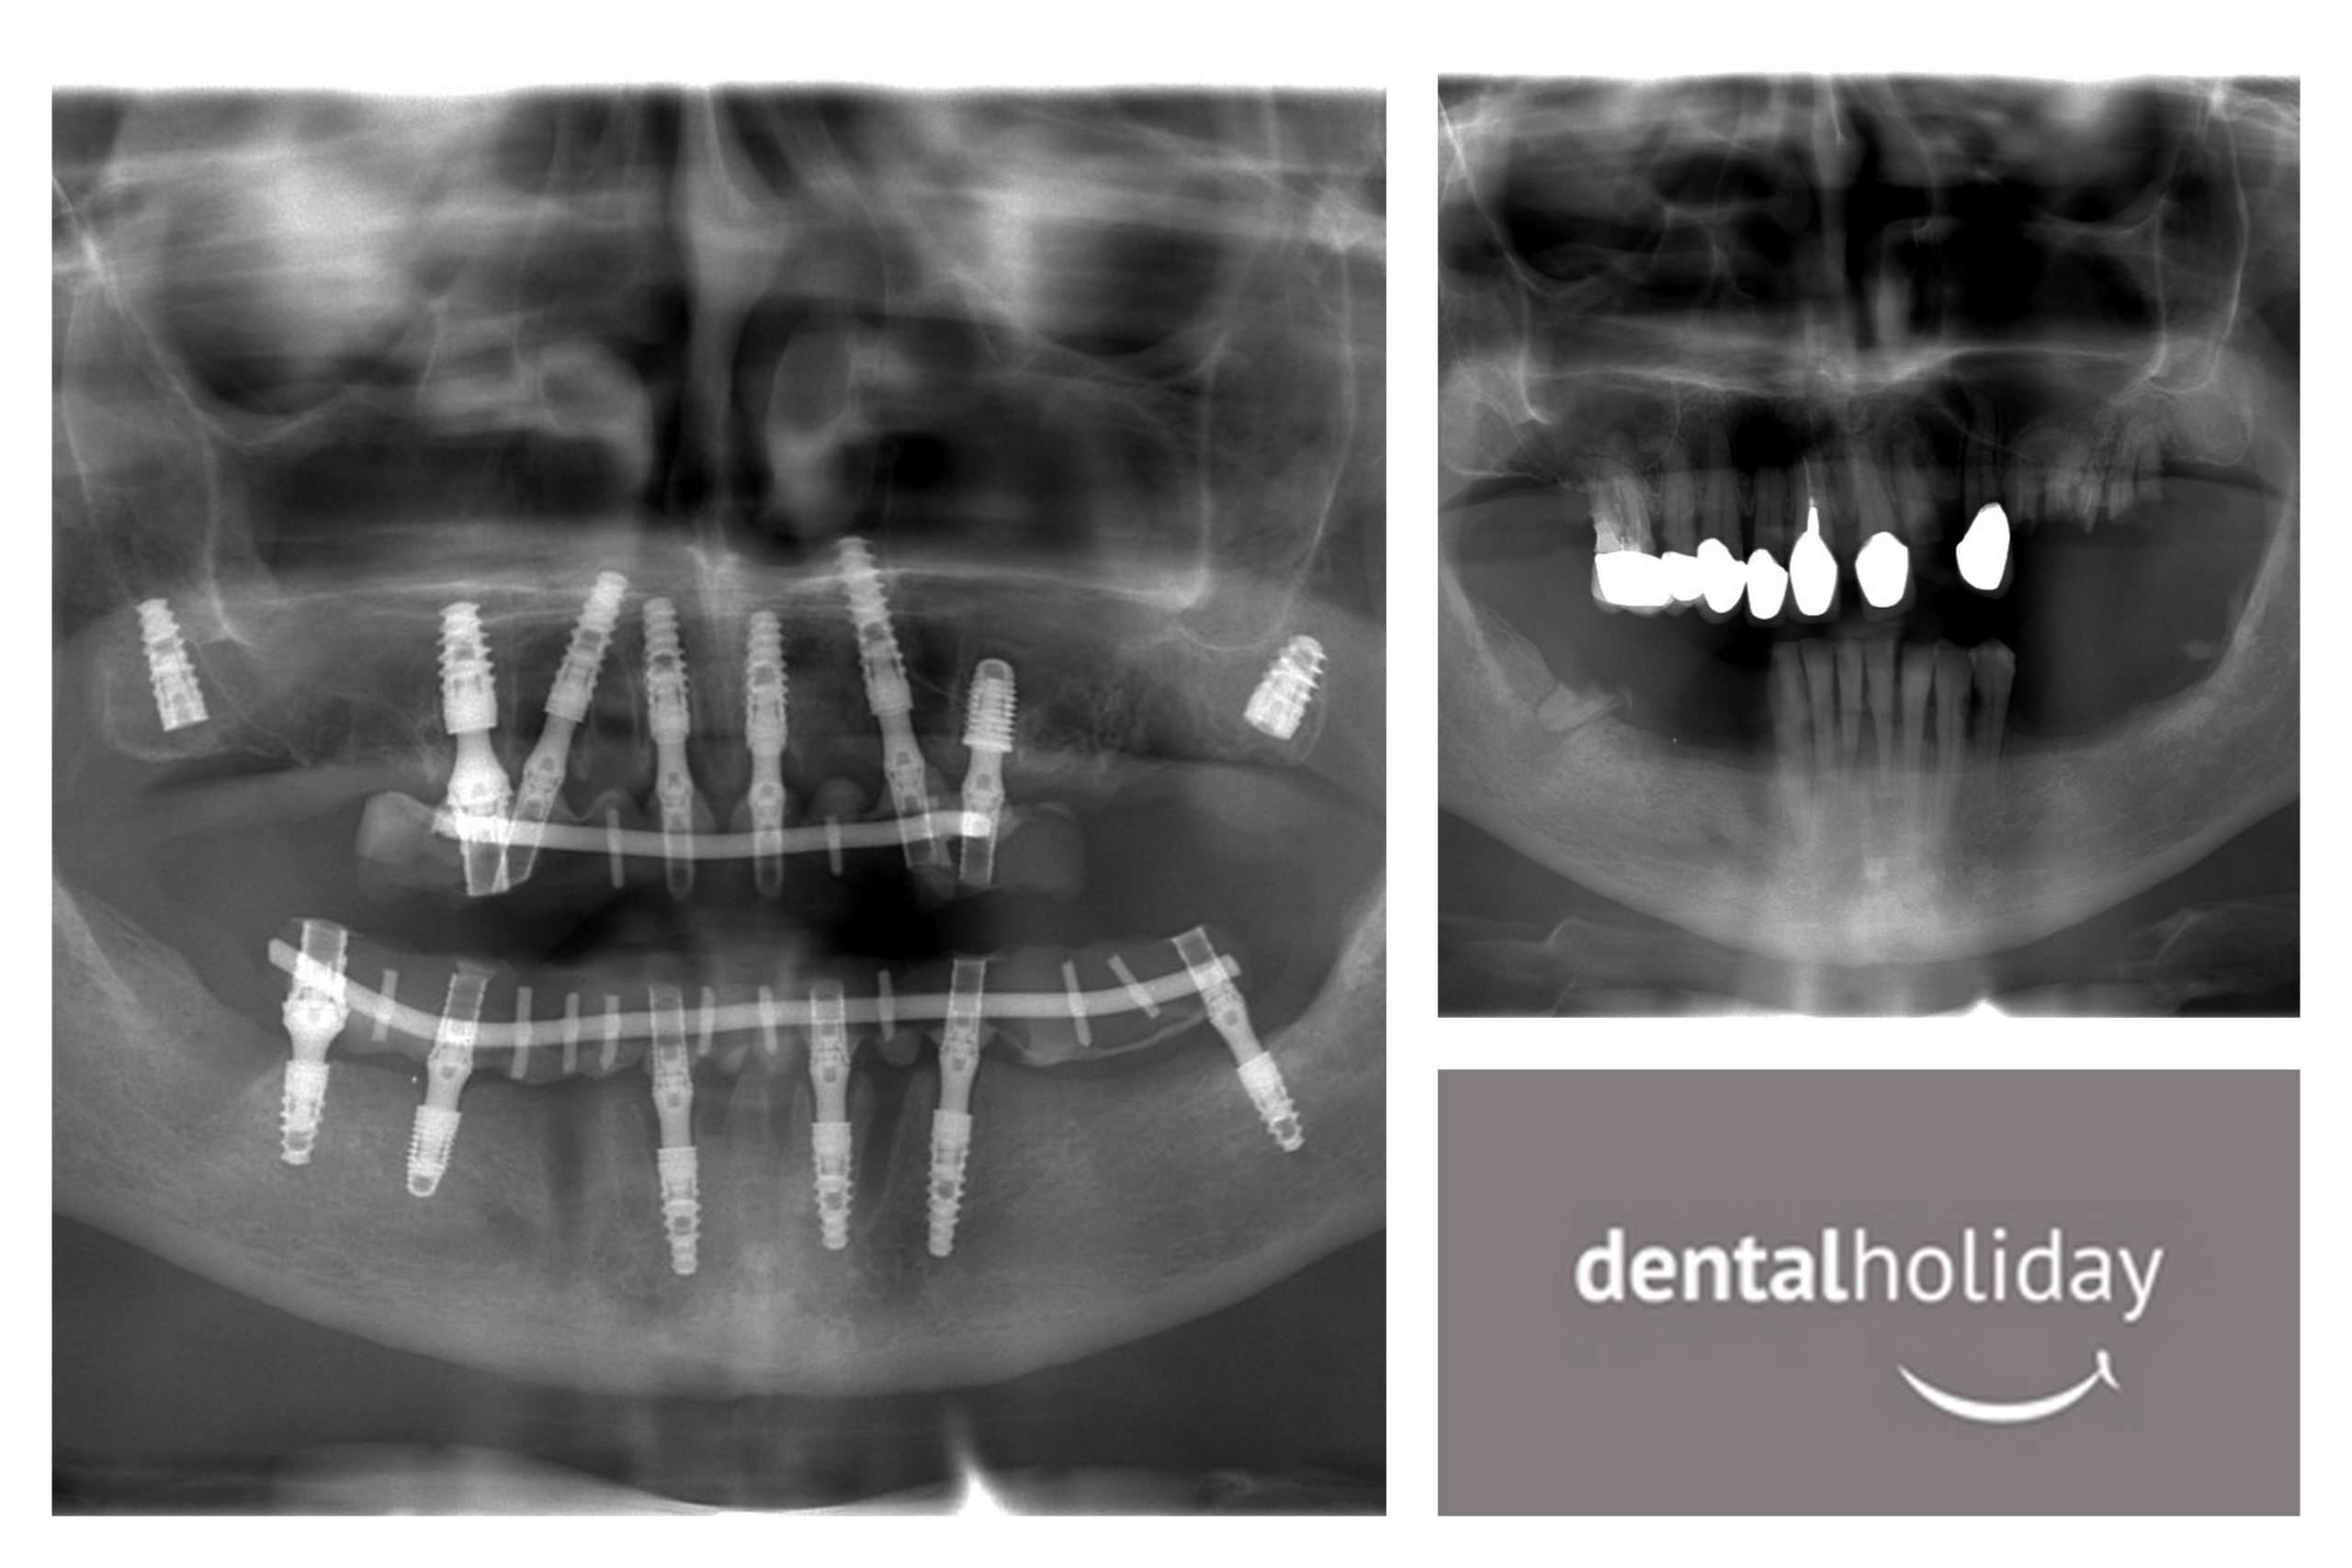

From the X-rays photographs, you can see the workmanship and care that went into this major dental overhaul.

For years I have had trouble with my teeth- back teeth when a child, large gaps as I got into later life. After researching for many months I came here in 2015. Today I leave here holding my head up with the perfect smile.

After having top and bottom implants for the first time in my life, I can look into the mirror and not feel ashamed. Everything here was done professionally, talked through everything, some discomfort but little pain. Healing went really well. I will be recommending this practice to all my friends. Thank you to everyone involved, you are all stars.”